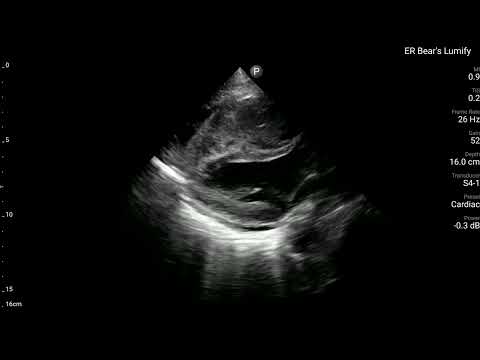

當時,在Bedside也有幫病患做echo。

可以清楚看到RV整團mass lesion,在PLAX打開color flow,在RV也沒有明顯flow。在PSAX view可清楚看到RV dilate with D-sign。A4C view更是清楚看到RV塞滿東西。不管是tumor還是thrombus,基本上已經造成RV strain(RV明顯dilate)。進而看到ECG上面的變化。